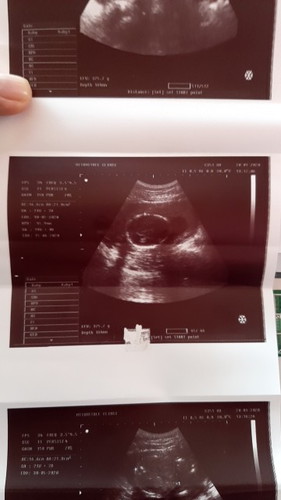

รูปบนส่วนหัวน้องค่ะ ส่วนรุปล่างมองไม่ออกค่ะ ส่วนนี่วิธีอ่านใบซาวด์

ได้แบบนี้มาเหมือนกันค่ะ มีคนบอกว่าเป็นส่วนกระโหลกศรีษะน้องค่ะ